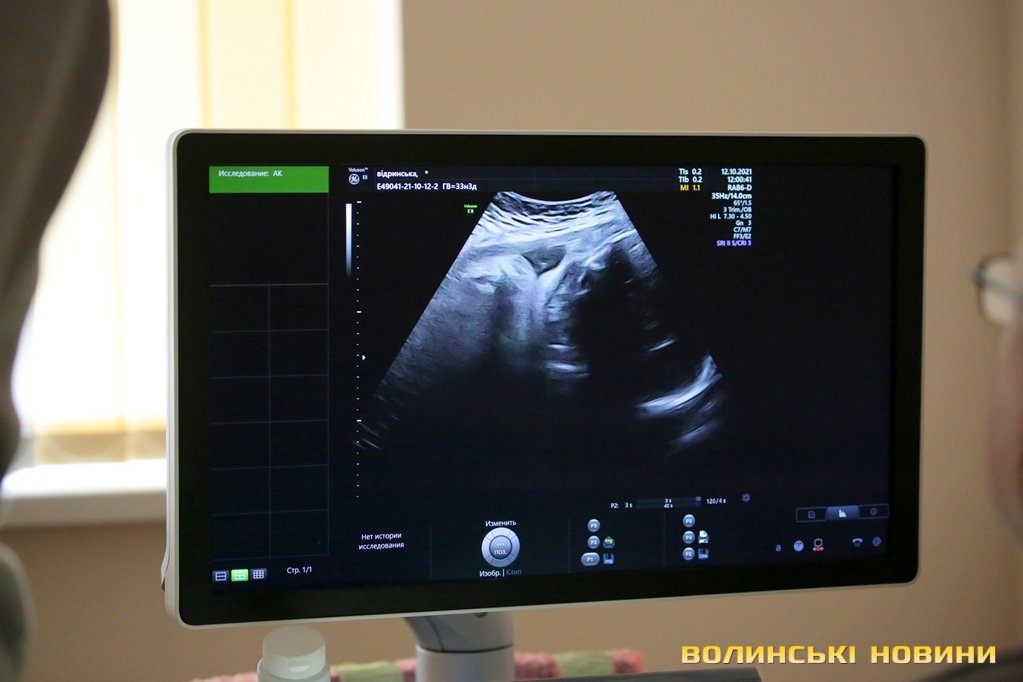

Волинський обласний перинатальний центр закупив найкращий УЗД-апарат з акушерської діагностики у світі – «Voluson E8BT21». Таких апаратів в Україні є лише три, адже його ціна зовсім недешева – шість мільйонів шістсот тисяч гривень. Однак його технології неабияк розширюють можливості у порівнянні з апаратами попередніх поколінь. Відтепер лікарі зможуть краще дослідити плід, адже новий апарат має функції 3D, 4D, Real time 4D та автоматичні програми з визначення анатомічних розмірів плода. А самі спеціалісти кажуть, що ніколи не бачили майбутню дитину так детально.

«Ми надаємо допомогу пацієнтам не лише з Волині, а й з інших областей, тому в нас виникла потреба в цьому УЗД-апараті. Він дає можливість більше дізнатися про функціональний стан плода та допомогає краще визначити анатомічну структуру майбутньої дитини. Його роздільна здатність включає в себе 3D-формат, що дає можливість виявити найменші тонкості структури плода. Це вкрай точна діагностика, яку можна проводити на дуже ранньому етапі вагітності», – зазначила Надія Щурук та додала, що апарат шукали протягом кількох місяців, придбавши його за шість мільйонів шістсот тисяч гривень.Інженер із обслуговування медичних приладів компанії «Protech Solutions» Максим Рудой, який встановлював УЗД- апарат у медичному закладі, розповів, що апарат «Voluson» розроблений в Австрії та відомий у світі, як УЗД-апарат номер один в акушерстві. Модель E8BT21 була випущена у 2021 році.

«Таких апаратів в Україні є лише три: два в Києві і тепер у Луцьку. Цей апарат найвищого рівня – Expert. Він має такі функції - 3D, 4D, Real time 4D, автоматичні програми з визначення анатомічних розмірів плода. В сучасних апаратах з’являється і штучний інтелект, коли машина може сама визначати, де лобно-потиличний розмір, шлуночок, велика цистерна. Але це все одно контролює людина. Апарат також обладнаний автоматичними програмами для дослідження серця. За рахунок того, що він обладнаний технологією Volume analysis calculation, є можливість отримати дослідження, які за допомогою 2D-сканування неможливо було би поміряти і відрізнити. Це безпрецедентно, що в Луцьку з’явився апарат такого рівня», – наголосив Максим Рудой.Першим випробував новенький УЗД-апарат завідувач відділення ультразвукової діагностики відділення Волинського обласного перинатального центру Сергій Грибчук.«Дуже важко описати враження. Ми щойно оглядали пацієнтку, картинка дуже відрізняється від тієї, яка була на попередніх апаратах УЗД. Я ще ніколи не бачив плід так детально, як на цьому апараті, це, зокрема, обличчя, внутрішні органи. На попередніх апаратах це неможливо було зробити. Тепер я можу більш детально описати стан майбутньої дитини. Можливості апарата дуже широкі для перинатальної діагностики. В ультразвуковій діагностиці важливі дві речі: спеціаліст та хороше обладнання. Обладнання ми точно маємо та й кажуть, що Грибчук – непоганий спеціаліст», – скромно розповідає лікар.Відзначимо, що завдяки цьому апарату Волинський обласний перинатальнйи центр зможе заключати угоди з міжнародними організаціями та проводити для них дослідження.